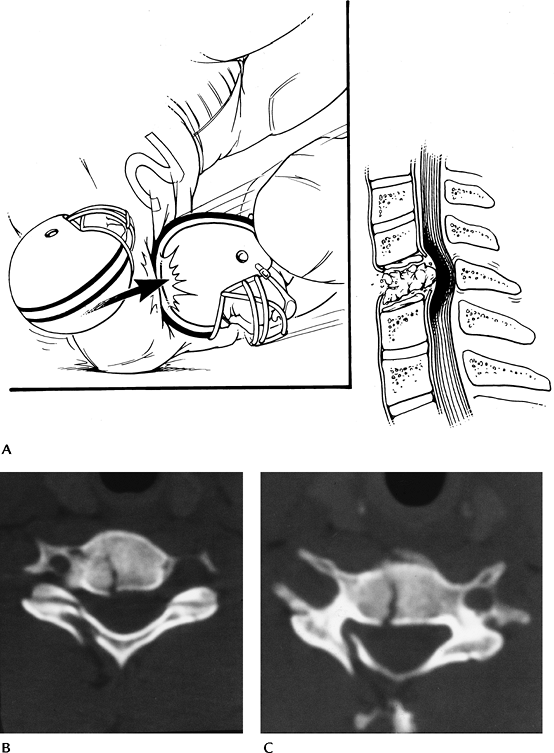

FIGURE 3-6 Vertical compression injuries. (A) Mechanism of injury. (B,C) Axial CT images of a burst fracture.